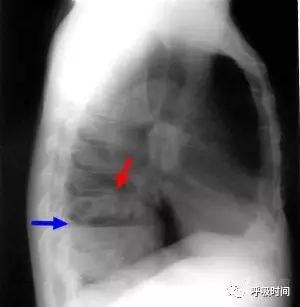

图 20 右肺下叶鳞癌:右肺下叶厚壁空洞影,内可见较大气液平(蓝箭头);肺门侧可见壁结节(红箭头)